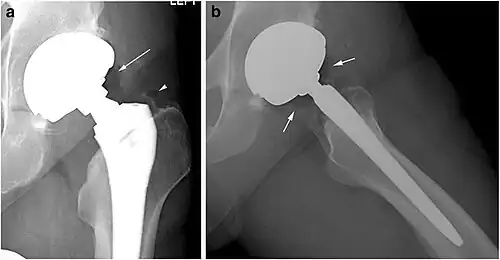

Pneumarthrosis is the presence of air in a joint. Its presentation on radiography is a radiolucent cleft often called a vacuum phenomenon, or vacuum sign.[7] Pneumarthrosis is associated with osteoarthritis and spondylosis.[8]

Pneumarthrosis is a common normal finding in shoulders[7] as well as in sternoclavicular joints.[9] It is believed to be a cause of the sounds of joint cracking.[8] It is also a common normal post-operative finding at least after spinal surgery.[10] Pneumarthrosis is extremely rare in conjunction with fluid or pus in a joint, and its presence can therefore practically exclude infection.[8]

-

X-ray of a hip with hip replacement and pneumarthrosis, in this case aseptic. -

A vacuum sign, or vacuum phenomenon, is a normal finding on shoulder X-rays.